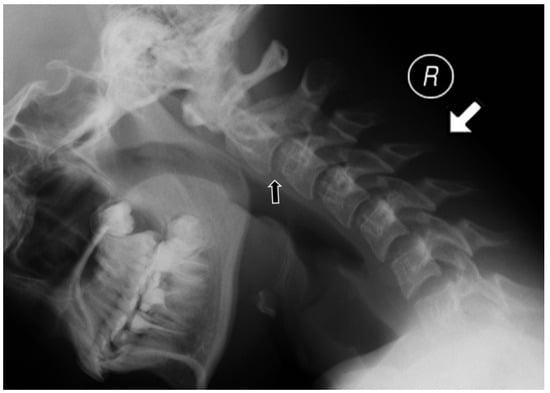

For the MRI examinations, a 1.5 T MRI scanner (Siemens Avanto) and the head/neck 8-channel coil were used. The protocol included coronal T2-weighted (w), axial T2w, sagittal T1w, T2w, T2w TIRM (turbo inversion recovery magnitude) sequences, and postcontrast T1w with fat saturation. Only one patient received intravenous contrast. At the atlanto-axial level, bone marrow oedema (BME), effusion, pannus, subluxations, cysts and erosions were looked for (Figure 2). At the subaxial level, BME, apophyseal joint ankylosis, SAS, and vertebral or disc hypoplasia were searched for [10,11]. Anterior AAS was diagnosed when a distance between the posterior aspect of the anterior arch of the atlas and the anterior aspect of the dens exceeded 5 mm [12] (Figure 3).

Three patients (9%) had abnormalities at the C1/C2 level. All had effusion (9%), anterior AAS was seen in 2 patients (6%), vertical AAS in 2 patients (6%), periodontoid pannus in 2 patients (6%) (Figure 2), and BME of the dens in 1 patient (3%). One patient received intravenous contrast and at C1/C2 level enhancement was seen. C1/C2 soft tissue involvement and BME were seen on MRI only.

Figure 2. Sagittal MRI, TIRM T2w sequence in a 12-year-old boy diagnosed with enthesitis-related arthritis shows BME in the dens (black arrow) and atlantoaxial effusion (white arrow). MRI—magnetic resonance imaging, TIRM T2w-turbo inversion recovery magnitude T2 weighted, BME—bone marrow edema.